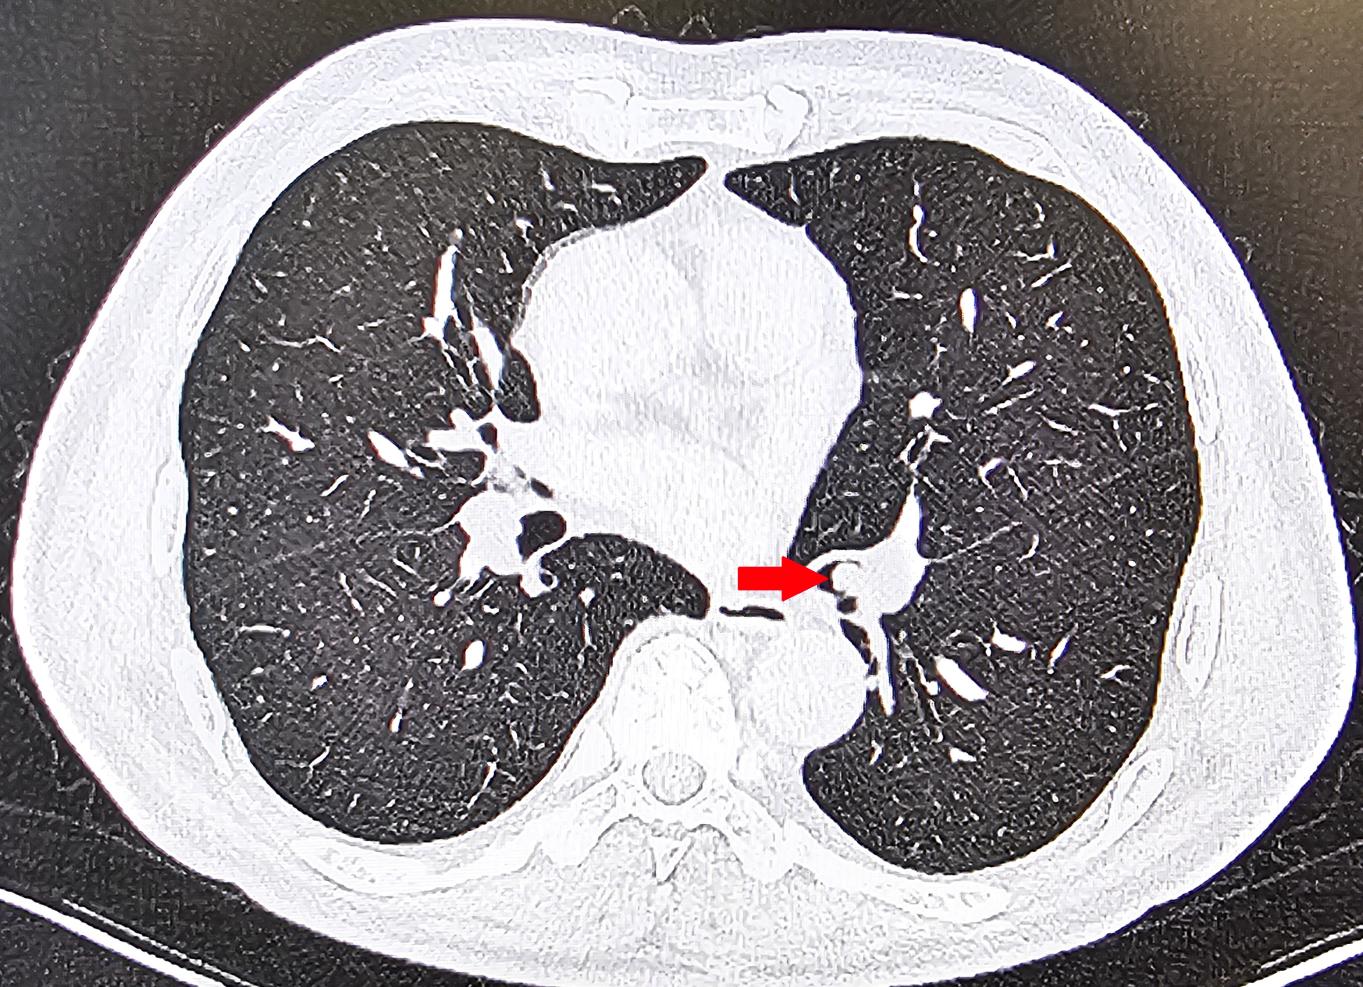

该院呼吸与危重症医学科医生团队接诊后,高度重视此病例。他们详细询问患者病史,仔细分析胸部 CT 影像,凭借专业经验,敏锐地发现患者左肺下叶支气管开口处存在可疑异物影。结合患者病史,医生判断为支气管异物。若不及时取出,异物极有可能引发肺部感染、阻塞性肺不张,甚至呼吸衰竭等严重并发症,严重威胁患者生命。